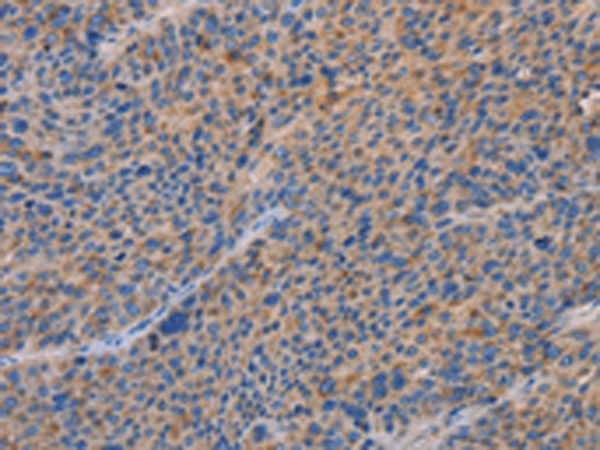

分类: 科研抗体货号: P11251别名: pf16; Repro-SA-1应用: IHC反应种属: Human, Mouse